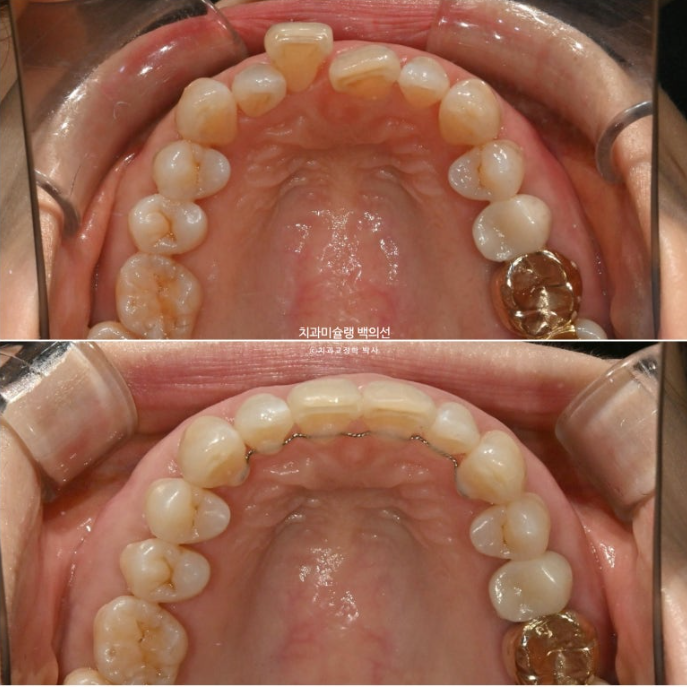

6개월 간 첫번째 세트 14개 장치를 모두 낀 후 모습입니다.

25.02

발치공간은 거의 개선이 되었으나 이를 뺐던 자리에는 부득이하게 블랙트라이앵글이 크게 보입니다.

교합은 좋고

배열상 미진한 부분들을 더 개선하고자 재제작에 들어갑니다.

25년 3월부터 9월까지 6개월간 14개 장치를 모두 낀 후 치료를 마무리 했습니다.

25.09

블랙트라이앵글 사이즈는 치간삭제를 통해 소량 줄였습니다.

교합은 완벽하고

배열은 좋습니다.

배열은 아주 깔끔합니다.